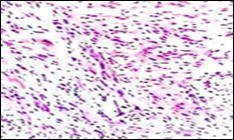

Figure 4.Soft tissue perineurioma composed of whorls and perivascular aggregates of neural cells with bipolar cytoplasmic processes, wavy, slender nuclei and commingled collagen fibres 13.